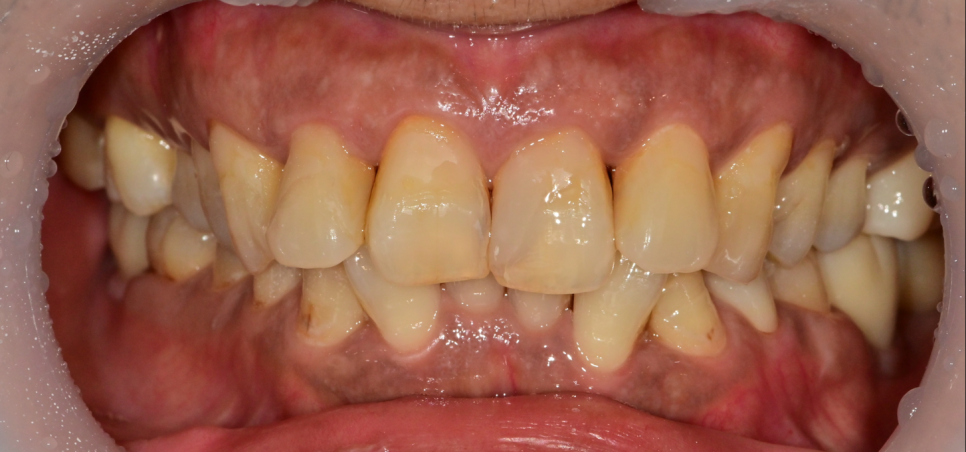

모든 보철 치료까지 끝난 후의 사진입니다.

마지막 날 환자분도 고생하셨겠지만 저 또한 뿌듯했습니다.

처음 치료를 시작했을 때 오랜 기간 동안 치료가 지속이 될까 걱정도 되었지만

환자분께서도 잘 도와주시고, 점점 내원 횟수가 늘며 치료받는 것도 많이 편해지시는 것 같아 보여 안심을 했던 기억이 있습니다.

치아가 없던 기간이 길었기 때문에 임플란트 수복 후에도 턱관절을 안정화 시키기 위해 시간이 필요합니다.